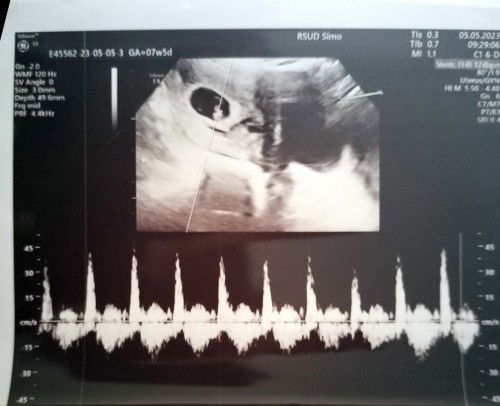

Hallo bunda.. disini ada yg hpl nya 19 Desember tp debay blm masuk panggul? Aku jd worry nih, krn dokter udah nyuruh ngasi keputusan buat lahiran normal atau sc.. btw aku hamil anak kedua bun, dulu anak pertama juga masuk panggul nya mepet mau lahiran baru masuk panggul.. #seriusnanya #bantusharing